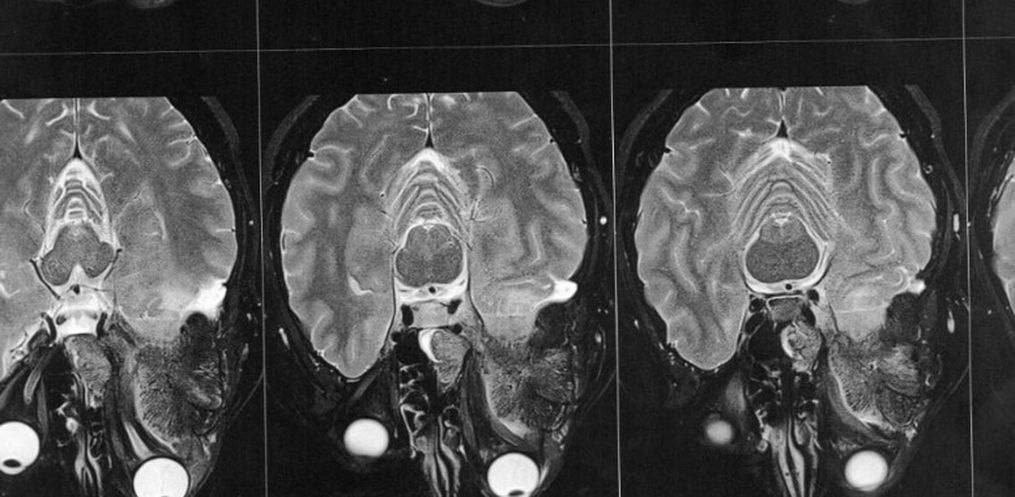

Então este médico solicitou exames de imagem (ressonância magnética e tomografia) para avaliar a situação, os quais foi constatado que o meningioma ainda está ali, e que continua empurrando o olho e se expandindo para outras áreas. Trata-se de um meningioma gigante (medindo 6 x 6,6 x 6 cm), que está localizado na placa do assoalho da fossa média e anterior.